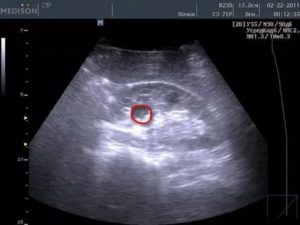

Типичный вид рака почки в нативную (до контрастирования) фазу. Хорошо заметен паренхиматозный узел в правой почке (в круге). Даже без усиления можно разглядеть его неоднородную структуру – с преобладанием мягкотканного компонента, а также с наличием менее плотных участков и включений кальция (красная стрелка).

В артериальную фазу становится хорошо различимой неоднородная структура опухоли, т. к. солидная ее часть (активная часть опухоли, хорошо снабженная сосудами) интенсивно усиливается и становится гиперденсной, а кистозная часть никак не накапливает контраст и остается той же плотности, что и в нативную фазу.

КТ-признаки рака (гипернефромы) почки в артериально-паренхиматозную фазу контрастирования.

На изображениях в верхнем ряду стрелкой красного цвета отмечено новообразование в виде узла с неоднородной структурой, синей стрелкой – простая киста в области нижнего полюса справа.

В нижнем ряду желтой стрелкой выделен мягкотканный компонент, накапливающий контраст и интенсивно усиливающийся. Зеленой стрелкой – кистозный компонент.